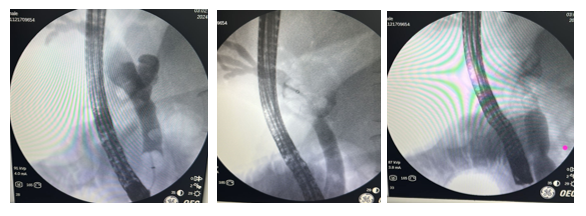

In addition, mild ectasia of the extrahepatic bile duct was documented with a linear image inside it, suggestive of a hepatobiliary endoprosthesis. However, the patient had no history of placement of said endoprosthesis, so the treating service considered the possibility of ascaris and decided to perform a new ERCP. During this procedure, a non-dilated intrahepatic bile duct and a dilated extrahepatic bile duct, measuring 10 mm, with a filling defect throughout the common bile duct, were observed (Annex 2). The bile duct was explored with an occlusion balloon and Dormia basket, extracting 5 ascaris one by one through the mouth.

Figure 1a&1b Magnetic resonance cholangiography: (t2 coronal right axial left section) Post cholecystectomy status, hepatic sub capsular collection that extends from the surgical bed between segments 5 and 6, without blood remains, mild ectasia of the extrahepatic bile duct with linear image inside suggestive of hepatobiliary endoprosthesis. Mild biliary ectasia, no gallstones identified.